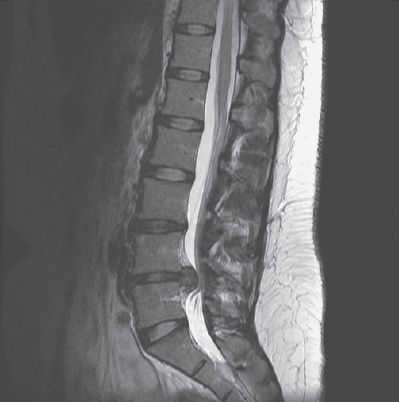

Kadar klinični izvidi nakazujejo herniacijo, vendar diagnoza ostaja nejasna, se lahko uporabijo slikovne preiskave za potrditev in natančnejšo opredelitev anatomskih sprememb. Magnetna resonanca (MR) je najpogosteje uporabljena slikovna diagnostična metoda. Omogoča natančen prikaz mehkih tkiv, vključno z diski, ligamenti in živci, ter pokaže tako mesto kot obseg premika tkiva. Pomembno je, da lahko prikaže tudi stik ali utesnitev živčnih struktur, kar bistveno vpliva na izbiro zdravljenja.

Slika, pridobljena z magnetno resonanco, ki prikazuje hernijo diska

Slika hernije, pridobljena z MR. Vir slike: N Engl J Med 2016;374:1564

Izvide slikovnih preiskav je vedno potrebno razlagati v povezavi s simptomi in funkcionalnim stanjem bolnika. Številni ljudje imajo na slikah vidne znake herniacije brez prisotnih bolečin ali omejitev, medtem ko imajo drugi izrazite simptome ob minimalnih strukturnih spremembah. Zato slikovna diagnostika ni samostojno diagnostično orodje, temveč dopolnilo kliničnemu pregledu. Učinkovita diagnostika združuje anamnezo, analizo gibanja, nevrološko testiranje in slikovne preiskave v celovito razumevanje odnosa med strukturnimi spremembami, biomehaniko in živčno-mišičnim nadzorom.

V določenih primerih, kjer se oseba skupaj s strokovnjakom odloči za operativen poseg, pa nam slikovna diagnostika pomaga izbrati najprimernejši poseg glede na stanje.